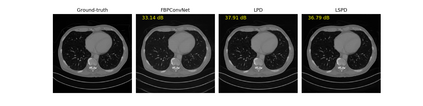

We propose a new type of efficient deep-unrolling networks for solving imaging inverse problems. Conventional deep-unrolling methods require full forward operator and its adjoint across each layer, and hence can be significantly more expensive computationally as compared with other end-to-end methods that are based on post-processing of model-based reconstructions, especially for 3D image reconstruction tasks. We develop a stochastic (ordered-subsets) variant of the classical learned primal-dual (LPD), which is a state-of-the-art unrolling network for tomographic image reconstruction. The proposed learned stochastic primal-dual (LSPD) network only uses subsets of the forward and adjoint operators and offers considerable computational efficiency. We provide theoretical analysis of a special case of our LSPD framework, suggesting that it has the potential to achieve image reconstruction quality competitive with the full-batch LPD while requiring only a fraction of the computation. The numerical results for two different X-ray computed tomography (CT) imaging tasks (namely, low-dose and sparse-view CT) corroborate this theoretical finding, demonstrating the promise of LSPD networks for large-scale imaging problems.